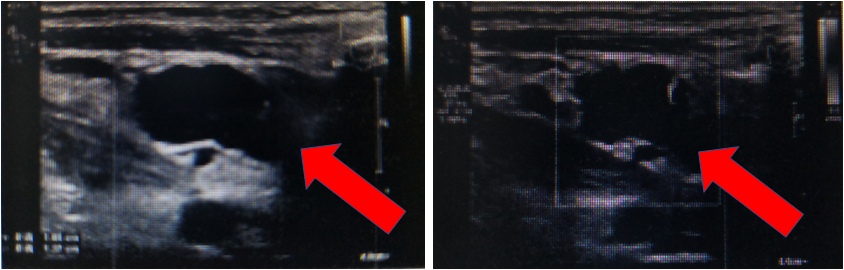

右颈及右锁骨上探及多个低回声,大者位于锁骨上,约2.2X1.3cm,周边可见少许血流信号。

2019.03.13右下肢静脉血管超声示:右侧小腿肌群间多条静脉不均匀扩张,管腔内探及不均低回声充填,压之不闭合,未见明显血流信号。提示:右侧小腿肌群间静脉血栓形成。